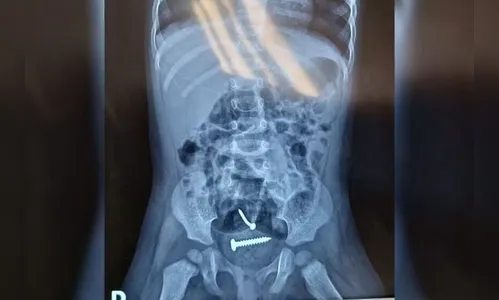

Após serem encaminhadas para o hospital, exames mostraram parafusos dentro do corpo da criança.

Segundo informações do delegado Júlio de Carvalho, a menina segue internada no Hospital de Urgência de Teresina (HUT). Ela passou por uma perícia médica e os resultados foram encaminhados para a delegacia. Os exames também apontaram lesões nas partes íntimas da criança.